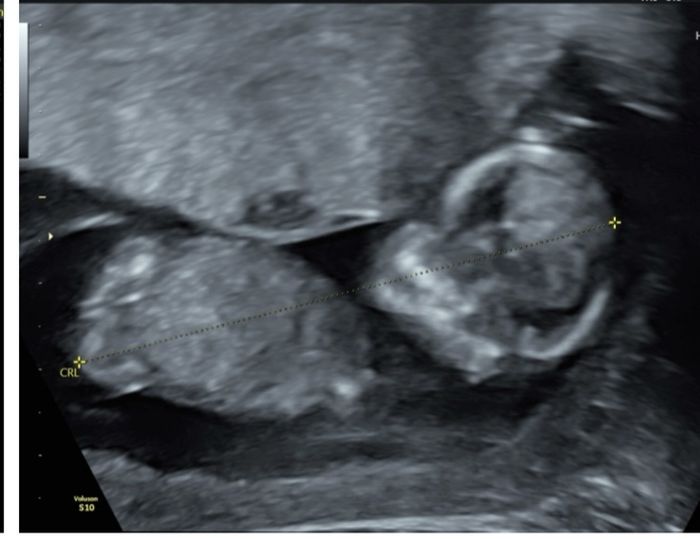

Nub theory, giochiamo un po’

Ciao ragazze, lunedì scorso ho fatto eco genetica a 11+5 ma bebè misurava 12 settimane, ho fatto dna fetale che dovrebbe arrivare questa settimana, ma nel frattempo per...